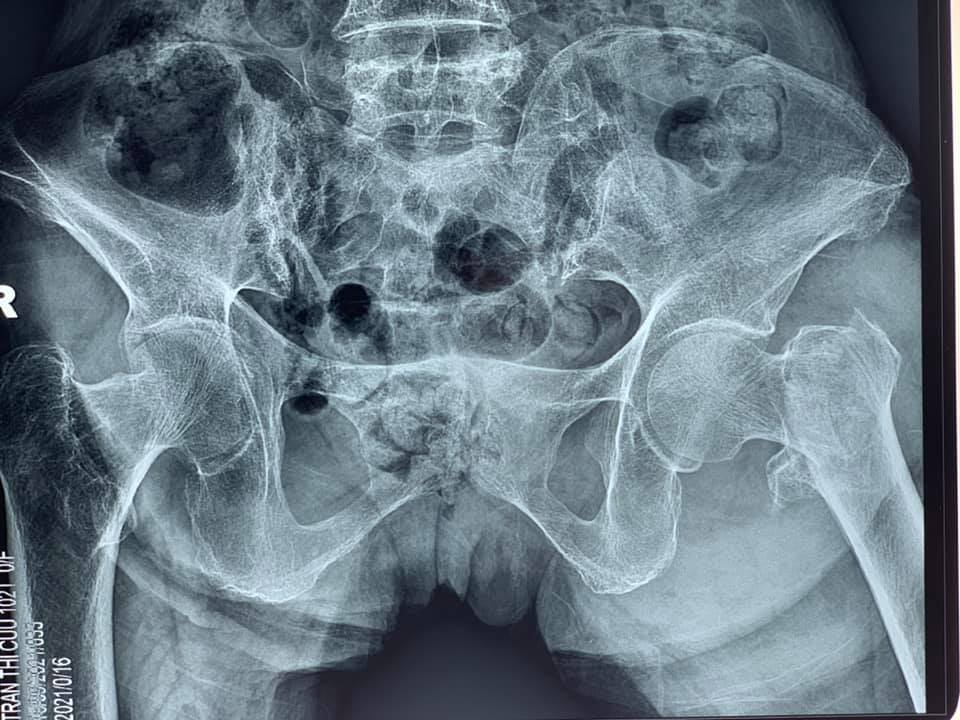

Gần đây nhất là trường hợp cụ bà Trần Thị C, 101 tuổi, ở Đông Quang – Ba Vì – Hà Nội bị gãy kín Liên mấu chuyển xương đùi trái do ngã ngày thứ nhất, bệnh nhân có bệnh lý tim mạch, tăng huyết áp, thiếu máu, suy kiệt.

Tiến hành làm các xét nghiệm, siêu âm, chụp X- quang, các bác sĩ nhận định đây là một trường hợp cần được phẫu thuật sớm, có thể cho bệnh nhân sớm ngồi dậy, tập luyện để tránh các biến chứng. Chỉ sau 1 ngày, bệnh nhân được phẫu thuật thay khớp háng trái nhân tạo bán phần không xi măng. Vượt qua những khó khăn trước phẫu thuật do tình trạng sức khỏe chung và bệnh lý nền kết hợp của bệnh nhân, kíp phẫu thuật đã kết hợp với kíp gây mê tiến hành thành công ca phẫu thuật, giúp cho người bệnh có cơ hội sớm bước đi trở lại.